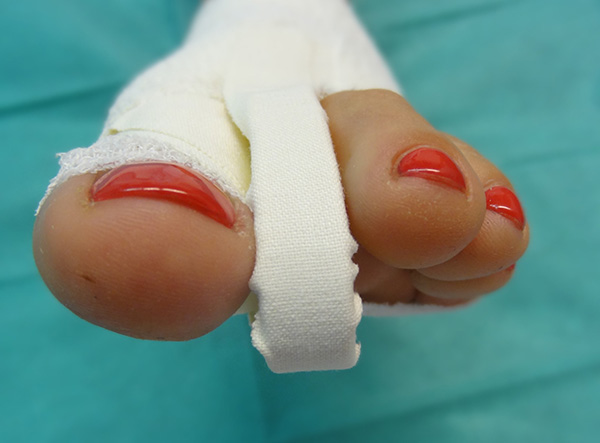

Sämtliche Operationsschritte werden über kleine Stichinzisionen durch die Haut durchgeführt. Isham beschrieb das Verfahren ohne Osteosynthese. Da es sich bei den knöchernen Korrekturen um mediale Closing wedge Osteotomien handelt, werden diese anschließend durch spezielle Zügelverbände (Tape) in Position gehalten. Postoperativ ist eine sofortige Vollbelastung im flachen Verbandsschuh möglich, der Wechsel auf Konfektionsschuhe erfolgt meist nach 4 bis 5 Wochen.

• Verbandmaterial zum Anlegen eines Redressionsverbandes (sterile Kompressen, sterile Watte, Haftbinde, Tape).

Postoperative Behandlung

• Röntgenkontrollen (a.p. und seitlich) postoperativ ohne Belastung – 6 Wochen, 3, 6 und 12 Monate postoperativ unter Belastung.

• Sofortige Vollbelastung des Fußes postoperativ im flachen Verbandschuh für 4 -6 Wochen. Anschließend Röntgenkontrolle unter Belastung.

• Verbandswechsel (vom Operateur selbst) 7, 14, 21 und 28 Tage postoperativ mit Freigabe nach 4-6 Wochen.